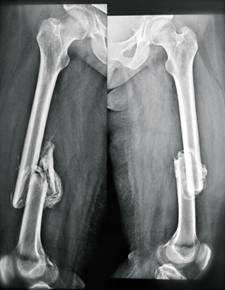

При поступлении пациентка находится в лежачем положении, при попытке вставания на ноги резкие болевые ощущения в области обеих бедер. При осмотре определяются комбинированные контрактуры обоих коленных (сгибание ограничено до 100°, разгибание до 160°) и голеностопных суставов (подошвенное сгибание ограничено до 100°, тыльное сгибание до 90°), патологическая подвижность в области обеих бедер. На рентгенограммах определяются консолидирующиеся в порочном положении переломы обеих бедренных костей с выраженным смещением отломков по длине и консолидированный в порочном положении перелом левой плечевой кости (Рис. 1,2). Разница в длине нижних конечностей составила 3 см.

Рис.1. Рентгенограмма пациентки С., 25 лет, на момент поступления

Рис.2. Рентгенограмма пациентки С., 25 лет, на момент поступления